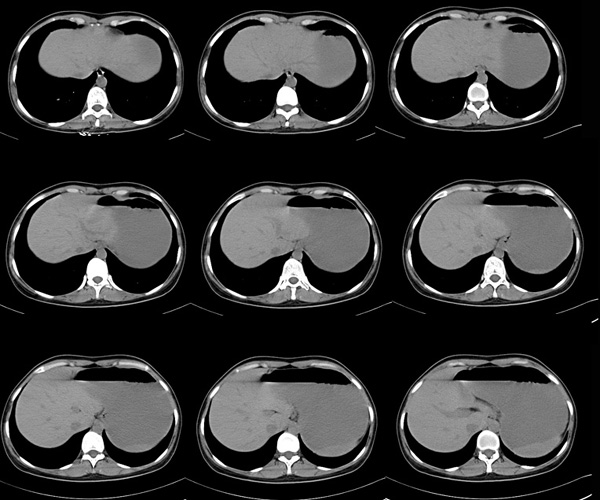

女性,28岁,停经3月,腹部膨隆1月,产前检查发现腹部占位

{肿块中心ct值27hu,增强后,动脉期、门脉期均无明显强化)

患者手术病理:腹腔囊性淋巴管瘤,象这样充满整个腹腔的的确很少见